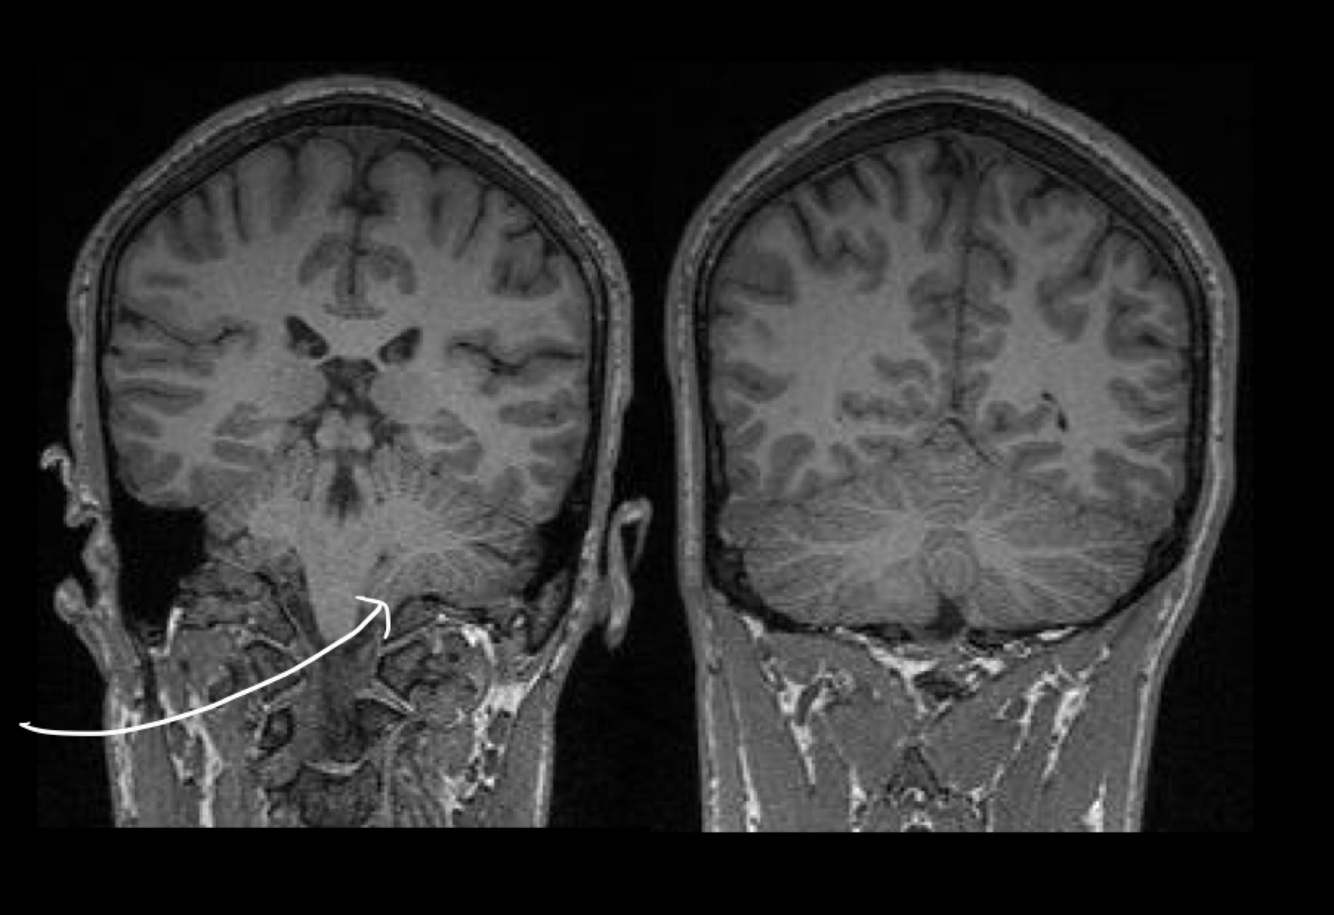

15

What is the arrow pointing at?

Cerebellar tonsils